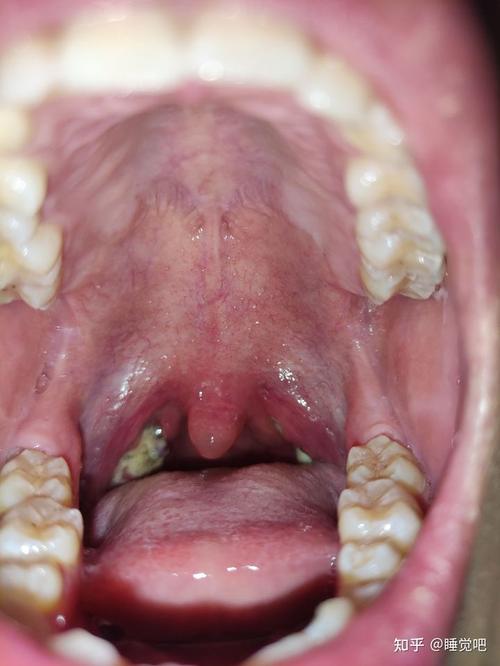

化脓性扁桃体炎症状,急性化脓性扁桃体炎

小儿扁桃体上有「脓」,就是化脓性扁桃体炎吗?

综合上述症状及舌像,诊断为急性化脓性扁桃体炎.

化脓性扁桃体炎图片

扁桃体炎化脓图片

扁桃体炎图片症状图